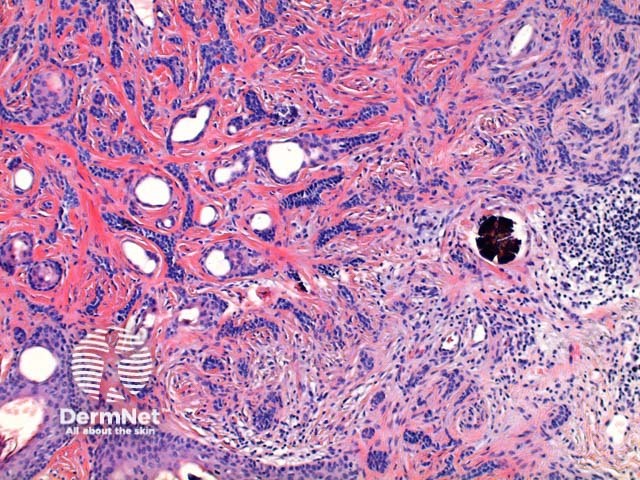

Scanning power view reveals a tumour comprised of multiple nodules situated within the dermis (Figure 1). Small horn cysts, abortive hair follicles and calcification are frequently seen (Figure 2). The stroma is denser and more cellular than with basal cell carcinoma, and there is often focal stromal cracking (Figure 2, arrow). Often pronounced bulbar differentiation may be seen, emulating the follicular bulb and papilla; these structures have been referred to as papillary mesenchymal bodies. (Figure 3, arrow).

Figure 3

Basal cell carcinoma – Distinction from basal cell carcinoma may at times be difficult even for experienced observers. The epithelium of trichoepithelioma demonstrates intimate integration with the surrounding matrix which is often cellular and fibromyxoid and show stromal clefting (Figure 2). In contrast, basal cell carcinoma typically exhibits at least some retraction (clefting) between the epithelial cells and the surrounding epithelium and may show mucin deposition. Papillary mesenchymal bodies (see figure 3 above) can serve as an important clue to trichoepithelioma. Immunohistochemistry is typically unhelpful but numerous stains are sited in the literature including Bcl-2, Ber-Ep4 and CD34.